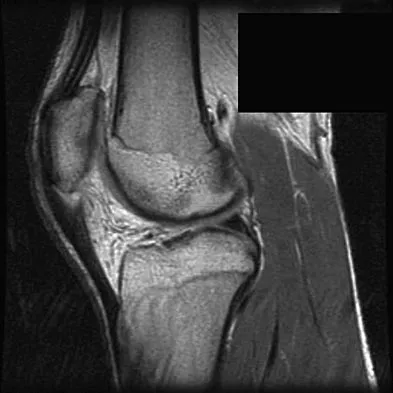

Question 76

A 17-year-old basketball player and pole vaulter who has had anterior knee pain for the past 18 months now reports a recent inability to jump. Based on the MRI scan shown in Figure 11, management should consist of

Explanation